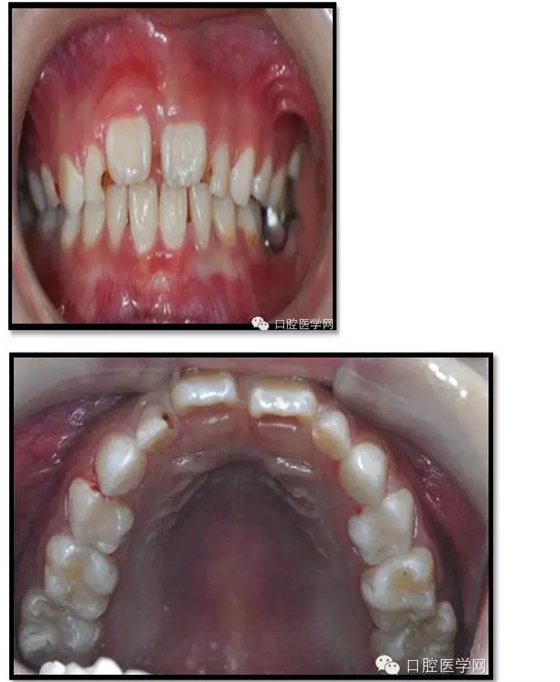

臨床檢查: 75OL齲洞, 舌側(cè)牙體完全劈裂斷端齊齦,探及大量軟化腐質(zhì)。頰側(cè)牙齦紅腫見瘺管,擠壓大量溢膿。叩(±),不松動。X線:75根管空虛,牙根吸收約1/2,根尖周及根分歧大面積透射影,35發(fā)育4期,骨硬板尚連續(xù);51殘根,唇側(cè)牙齦瘺管,叩(±),不松動。X線:51牙根吸收約1/2,根尖周低密度影。

85O、84DO充填體邊緣不密合,叩(±),不松動。84頰側(cè)牙齦略紅腫。X線:84遠(yuǎn)中根及髓室底完全吸收,根分歧透射影,近中根內(nèi)側(cè)見外吸收,44上方骨硬板連續(xù)。85近中根完全吸收,髓室底吸收,根分岐透射影,遠(yuǎn)中根管內(nèi)見根充影像。45發(fā)育4期,骨硬板連續(xù)。

55OL、65OL、74O、53DL齲洞,叩(-),不松動,齦無異常。

16OL、46OB、26O、36OB窩溝探及淺齲壞,叩(-),不松動,齦無異常。